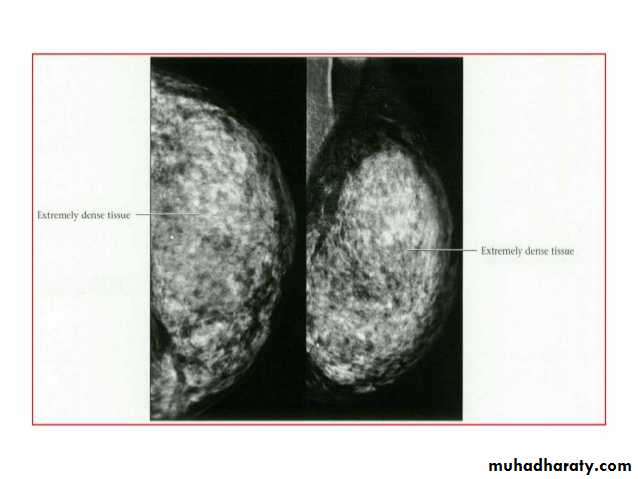

Breast density & who can U detect a mass lesion

Your mammogram report must take in consideration & assessment the breast density. Breast density is based on how fibrous and glandular tissue tissues are distributed in your breast, vs. how much of your breast is made up fatty tissue.

Dense breasts are not abnormal, but they are linked to a higher risk of breast cancer. We know that dense breast tissue can make it harder to find cancers on a mammogram. Still experts do not agree what other tests, if any, should be done in addition to mammograms in women with dense breasts who aren’t in a high-risk group (based on gene mutations, breast cancer in the family, or other factors